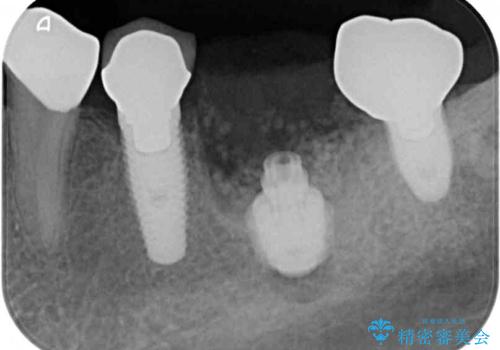

そのため、当院に新しく導入した手法により、抜歯をした日にインプラントを埋入し、そのままを仮歯を装着することで、他の歯への負担を軽減する計画を立てました。

インプラント埋入時に植立具合の安定性を測定したところ、十分な数値が得られたため、速やかに仮歯を装着して咬合回復をさせることができました。

抜歯を含めた外科処置を1回に抑えることができ、あっという間に治療を終えることができました。